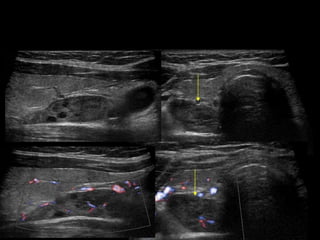

QUISTE DEL 2º ARCO BRANQUIAL

QUISTE DEL 2ºARCO BRANQUIAL • Remanente quísticO relacionada con alteraciones en el desarrollo del segundo arco branquial • fístula del seno- o quiste. • Ubicación típica de quiste : relacionado con la con vaina carotídea, la glándula submandibular, y el ECM • Unilocular, anecoica con paredes delgadas y refuerzo posterior, ecos internos debiles. • No vascularizado.